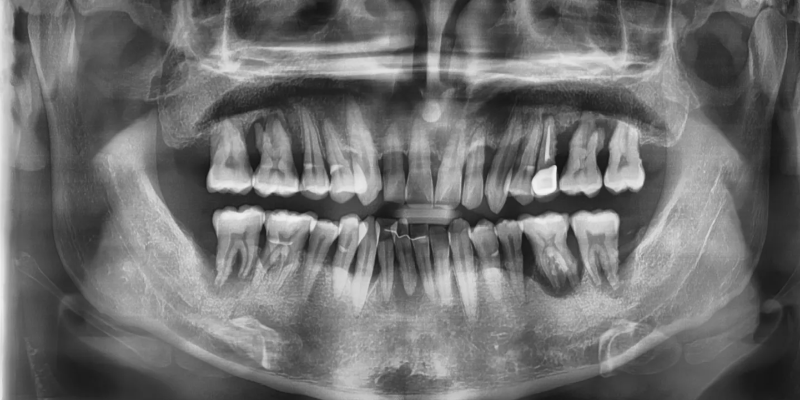

초진 파노라마 사진에서 만성 치주염으로 인해

치조골 소실이 매우 심한 상태가 확인되었습니다.

앞니부위는 교정을 하여 치아를 먼저 배열하고

어금니 부위는 발치 후 임플란트를 하기로 계획하였습니다.